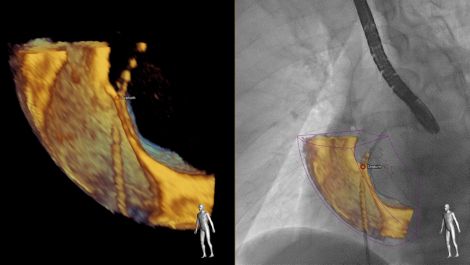

Photo Gallery Of New Imaging Technologies At Rsna 2019 Imaging Technology News

Echonavigator Interventional Tool Fusing Live X Ray And Live Echo Philips Healthcare